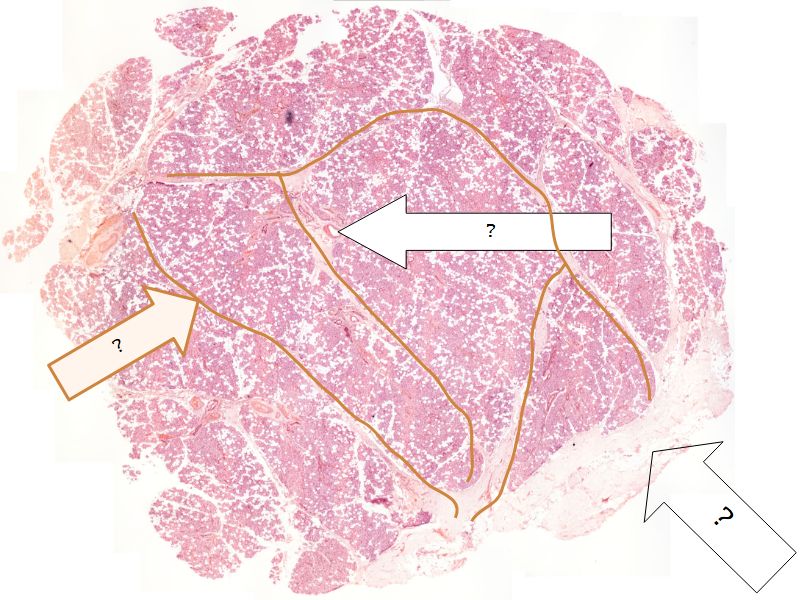

Fill in all the missing labels, and assess as you move through the slides. Answers on the down slide. It is important to do this using pen and paper, and not just glance through the images.